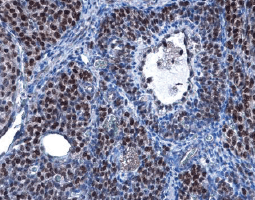

| 心臟的功能為泵驅動連續的血液柱通過脈管系統,心脏功能障碍和疾病可能是由于冠状动脉狭窄(动脉粥样硬化)、瓣膜性心脏病、影响心肌的心肌病、由于传导受损引起的心律失常以及感染或炎症过程(例如心内膜炎、心肌炎或心包炎), 心脏和血管疾病的临床和社会负担使心血管生物学研究成为重中之重。 |